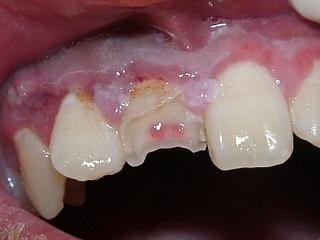

複雑性歯冠破折:露髄を伴い、エナメル質、象牙質、セメント質に及ぶ破折 (図2、3)

図3

複雑性歯冠破折の場合(図2,3)

強い冷温水痛、あるいは、強い自発痛があります。

歯髄保護をしたのち、レジン樹脂などで破折部の修復を行います。

しかし歯髄への傷害が大きい場合には歯髄除去(抜髄)が必要に成ります。